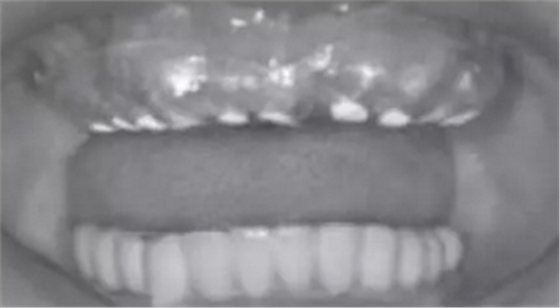

1.2.3治療過程:先行微創(chuàng)拔除14、13、21、22、23、24及25,搔刮拔牙窩去除炎癥組織,常規(guī)制作一副上頜過渡義齒(圖4,5)。2個(gè)月拔牙術(shù)后復(fù)診,利用上頜過渡義齒作為個(gè)性化托盤取上頜模型并翻制石膏模型,在石膏模型上根據(jù)過渡義齒標(biāo)出各個(gè)牙位,同時(shí)利用壓膜機(jī)制作放射性模板(如圖6)?;颊吲宕鞣派湫阅0迮臄z全景片及CBCT(如圖7、8)。

圖7 佩戴放射性模板口內(nèi)照